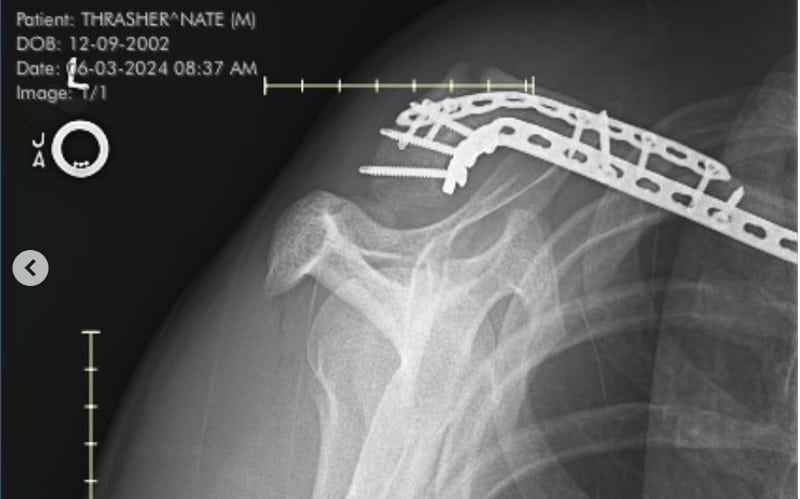

Mais pourquoi annonce-t-il qu’il roulait à 60 % de son potentiel ? Nate Thrasher a fourni plus d’informations lui-même sur son compte Instagram, en révélant qu’il avait subi une grosse chute avant le deuxième round d’Hangtown et qu’il avait roulé diminué. Et effectivement, une radiographie réalisée lundi matin a montré qu’il souffrait d’une fracture de la clavicule, et qu’en plus il avait plié une plaque qui se trouvait déjà sur l’os ! Terminer deux manches dans les points d’une course pro dans ces conditions, chapeau l’artiste ! Après deux courses, Nate  Thrasher occupait la neuvième place du classement avec 46 points. Il n’y a pas encore de date prévue pour son retour à la course.

Son message sur Instagram : « Ce n’est pas le message que je voulais écrire. La semaine dernière, j’ai eu un grave accident à la GOAT farm, et j’ai fait tout ce que je pouvais pour rouler à Hangtown. Ce n’était vraiment pas facile, mais j’ai fait de mon mieux pour m’en sortir. Hier, j’ai passé une radiographie et j’ai découvert que je m’étais cassé la clavicule et que j’avais également plié la plaque dessus. Je vais le faire réparer demain et commencer ce qui devrait être une récupération rapide ! Extrêmement déçu, mais je devrais bientôt revenir aux courses ! Merci à tous ceux qui me soutiennent. » Des durs, les mecs…